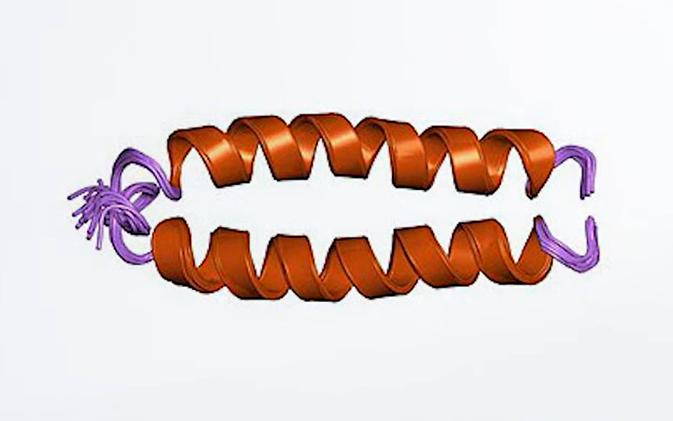

融合蛋白是什麼?

融合蛋白的概念其實很直覺:把兩種以上、功能不同的蛋白質,用基因工程的方式「接起來」,讓它們成為同一個分子。

融合蛋白雖然潛力強大,但要製造出來可一點都不簡單。它並不是用膠水把兩段蛋白質黏在一起就好。「融合」這件事,得從最根本的設計圖,也就是 DNA 序列就開始規劃。

我們體內的大部分蛋白質,都是細胞照著 DNA 上的指令一步步合成的。所以,如果科學家想把蛋白 A 和蛋白 B 接在一起,就得先把這兩段基因找出來,然後再「拼」成一段新的 DNA。

不過,如果你只是單純把兩段基因硬接起來,那失敗就是必然的。因為兩個蛋白會互相「打架」,導致摺疊錯亂、功能全毀。

這時就需要一個小幫手:連接子(linker)。它的作用就像中間的彈性膠帶,讓兩邊的蛋白質能自由轉動、互不干擾。最常見的設計,是用多個甘胺酸(G)和絲胺酸(S)組成的柔性小蛋白鏈。

設計好這段 DNA 之後,就能把它放進細胞裡,讓細胞幫忙「代工」製造出這個融合蛋白。接著,科學家會用層析、電泳等方法把它純化出來,再一一檢查它有沒有摺疊正確、功能是否完整。

如果一切順利,這個人工設計的融合分子,就能像自然界的蛋白一樣穩定運作,一個全新的「人造分子兵器」就此誕生。